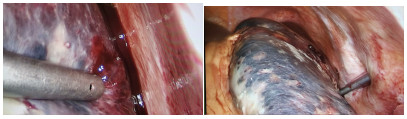

A preliminary study on percutaneous transhepatic drainage combined with sequential percutaneous nephroscopy in treatment of refractory liver abscess

Changhu DUAN, Xiaochen LIU, Jianlong DING, Jianfeng DUAN, Xirong ZHAO, Fan YANG, Ling WU, Lifei ZHAO, Sheng TAI

2021, 37(11): 2622-2625. DOI: 10.3969/j.issn.1001-5256.2021.11.026

Abstract(1123) HTML (227) PDF (2925KB)(75)

Abstract:

Objective  To investigate the clinical effect of percutaneous transhepatic drainage combined with sequential percutaneous nephroscopy for necrosectomy and drainage in the treatment of refractory liver abscess after transcatheter arterial embolization (TACE).  Methods  A retrospective analysis was performed for three patients with refractory liver abscess after TACE in The Affiliated 3201 Hospital of Xi'an Jiaotong University School of Medicine from January 2018 to December 2020, and among the three patients, one had the formation of liver abscess after TACE for hepatic metastases after pancreaticoduodenectomy, one had liver abscess after repeated TACE for massive hepatocellular carcinoma, and one had secondary liver abscess after TACE for traumatic hepatic rupture. All three patients received percutaneous transhepatic drainage and sequential percutaneous nephroscopy for the treatment of refractory liver abscess, and their specific treatment process was summarized.  Results  All three patients were diagnosed with refractory liver abscess based on CT, routine blood test, procalcitonin, blood culture, and clinical manifestation. Percutaneous transhepatic catheterization under the guidance of conventional ultrasonography or CT and effective antibiotics had an unsatisfactory therapeutic effect, and after sequential percutaneous nephroscopy was performed for necrosectomy and drainage, liver abscess was cured and the patients had good prognosis.  Conclusion  For refractory liver abscess after TACE, when routine puncture treatment has an unsatisfactory therapeutic effect or a patient cannot tolerate surgical operation, percutaneous transhepatic drainage combined with sequential percutaneous nephroscopy is safe and effective in the treatment of refractory liver abscess.